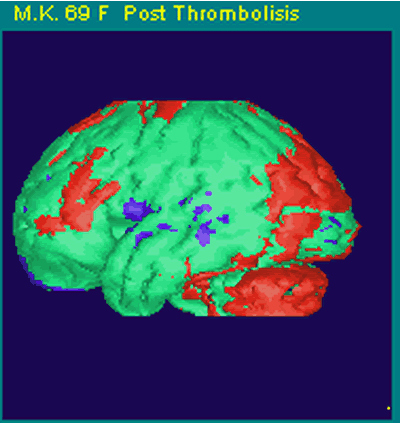

La paciente es una mujer de 69 años que consultó a la Clínica Las Condes por una afasia receptiva completa (afasia de Wernicke) de dos horas de evolución. La paciente tenía antecedentes de arritmia cardíaca (fibrilación auricular) pero no estaba recibiendo sus medicamentos de anticoagulación. De inmediato se efectuó una tomografía axial computada (TAC) cerebral, la que no mostró evidencias de hemorragia ni cambios precoces de infarto cerebral. En ese momento se decidió que la paciente era una buena candidata para trombolisis y se comenzó una infusión endovenosa de tPA (10% dosis según peso en bolo y 50% de dosis total en 45 minutos) con una dosis reducida de trombolisis EV. También se le inyectó el radiofármaco Tc99mHMPAO para posteriormente obtener un NeuroSPECT inicial. A continuación se efectúo una angiografía cerebral la que mostró una oclusión de la rama angular de la arteria cerebral media izquierda, probablemente de origen cardioembólico (Figura Ia). Se avanzó un microcatéter hasta la oclusión (Figura 1b) y se comenzó la trombolisis IA local, al mismo tiempo que se detuvo la infusión endovenosa de tPA después de haber recibido una dosis total de 24mg tPA EV. Al cabo de una hora, fue posible obtener una completa recanalización del vaso ocluido inyectando IA un total de 20 mg de tPA. Inmediatamente de haber recanalizado este vaso (Figura 1c y 1d), la paciente se recuperó de su afasia. El examen de NeuroSPECT pre-trombolisis demostró una zona de hipoperfusión profunda en el territorio de la arteria angular Figs. 2a y 2b.. La paciente ingresó a la Unidad CerebroVascular para un manejo médico especializado incluyendo manejo hemodinámico, anticoagulación después de las primeras 24 horas y manejo de su arritmia cardíaca. Un segundo NeuroSPECT de control a las 24 horas post-trombolisis, demostró una completa recuperación de la perfusión cerebral en el territorio de la arteria ocluida (Figura 2c y 2d). Por último, una resonancia magnética de cerebro (Figura 3) no reveló ninguna evidencia de infarto cerebral. La paciente fue dada de alta a los siete días sin ningún déficit neurológico.